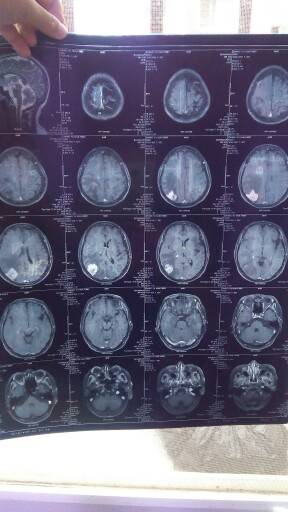

妈妈肺部和脑部肿瘤消失了